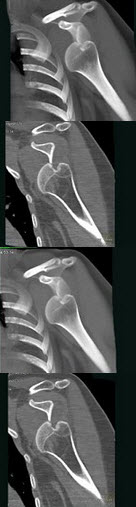

61、单项选择题

男,52岁,肩痛四月余,手臂旋转时疼痛加剧,结合影像,最可能的诊断是()

A.软骨瘤

B.骨结核

C.冈上肌腱钙化

D.骨囊肿

E.骨脓肿